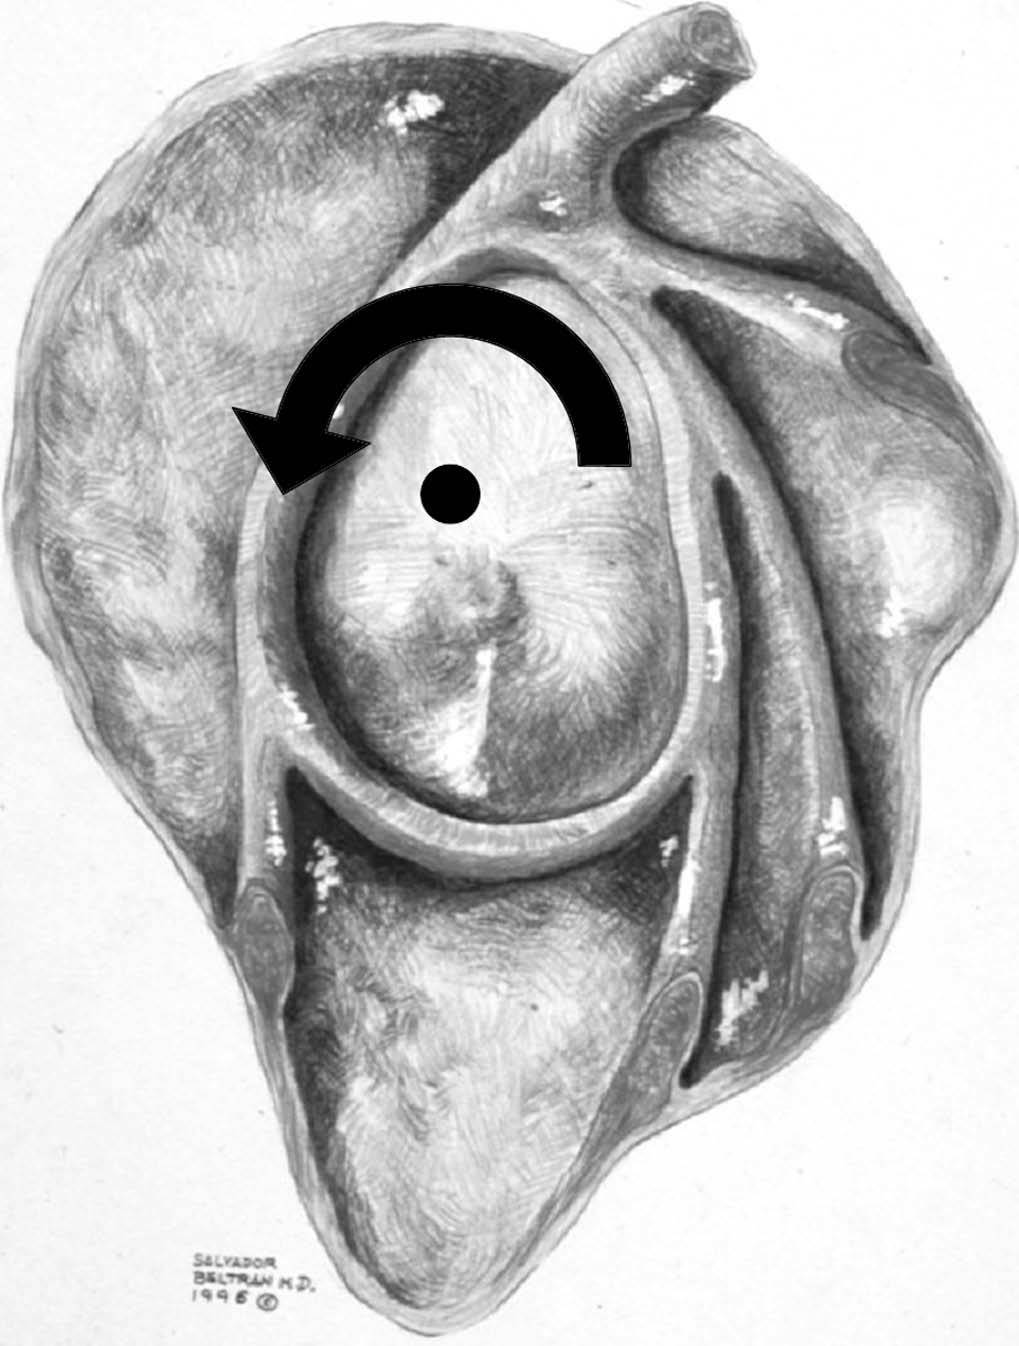

Con el brazo en abducción a 90 grados, el hombro puede realizar una rotación externa, a partir de la horizontal, de aproximadamente 100 a 120 grados, y una rotación interna de aproximadamente 100 a 120 grados, dependiendo del entrenamiento. Durante este movimiento la cabeza humeral tiene su punto de rotación en el centro de la cavidad glenoidea y el trocánter describe un arco centrado en este punto (fig. 5).

Fig. 5.--Esquema de la cavidad glenoidea y la cápsula donde se puede observar el centro de rotación normal de la cabeza humeral con el brazo en abducción (punto negro) y el arco de rotación del trocánter (flecha curva).

A fin de entender la patofisiología de la inestabilidad glenohumeral en el atleta lanzador, es importante conocer el movimiento normal de la articulación durante la acción de lanzamiento13. Con pequeñas diferencias, el lanzamiento por encima de la cabeza es muy similar en diferentes deportes, incluyendo el tenis, voleibol y béisbol14,15. Hay seis fases del movimiento en el lanzamiento por encima de la cabeza (fig. 7): preparación, primera elevación, segunda elevación, aceleración, deceleración y seguimiento. Durante la fase de preparación, hay una mínima sobrecarga y actividad muscular del hombro; al final de esta primera fase, el hombro se halla en una rotación interna mínima y una abducción discreta (fig. 7, posiciones 1 y 2). Durante la fase de primera elevación, el hombro se eleva a 90 grados de abducción y 15 grados de aducción horizontal (el codo se encuentra en posición posterior al plano coronal del torso) (fig. 7, posición 3); durante esta fase hay una activación precoz del músculo deltoides y una activación tardía de los músculos del MR, con la excepción del subescapular. Durante la segunda elevación, el hombro termina en una máxima rotación externa de 170 a 180 grados, manteniendo una abducción de 90 a 100 grados. La abducción de 15 grados cambia a 15 grados de aducción horizontal (fig. 7, posición 4); la escápula se retrae para facilitar esta posición y provee una base estable para la cabeza del húmero. La combinación de abducción y rotación externa fuerzan una traslación posterior y superior de la cabeza humeral en la cavidad glenoidea. Cuanto más forzada es la rotación externa, más superior y posterior es la traslación de la cabeza humeral (fig. 8). En términos de béisbol, el conseguir una máxima rotación externa, forzando la cabeza humeral en sentido posterior y superior, se conoce como «encontrar la zona». La actividad del deltoides disminuye, mientras que la actividad del MR alcanza su punto máximo. Durante la parte final de esta fase, los músculos subescapular, latisimus dorsi, pectoral mayor y serrato anterior aumentan su actividad. Durante la fase de deceleración, una vez se ha lanzado la pelota, la energía que no se ha transferido a la pelota se disipa. Esta fase comienza con un cese de la rotación humeral a cero grados; la abducción se mantiene a 100 grados y la aducción aumenta a 35 grados. Todos los músculos se contraen violentamente con contracción excéntrica, permitiendo una deceleración del brazo. Durante esta fase, la sobrecarga articular es muy alta posterior e inferiormente, y las fuerzas de compresión son igualmente importante a través de la contracción del bíceps. Durante la última fase de seguimiento, el cuerpo se desplaza hacia delante junto con el brazo, hasta que el movimiento cesa. La rotación disminuye a 30 grados, la aducción horizontal aumenta a 60 grados y la abducción se mantiene a 100 grados, mientras disminuyen las fuerzas de sobrecarga (fig. 7, posición 6).

Fig. 8.--El centro de rotación (punto negro) y el arco de rotación del trocánter (flecha curva) se trasladan hacia atrás y hacia arriba durante la hiper rotación externa del hombro con el brazo en abducción a 90 grados.